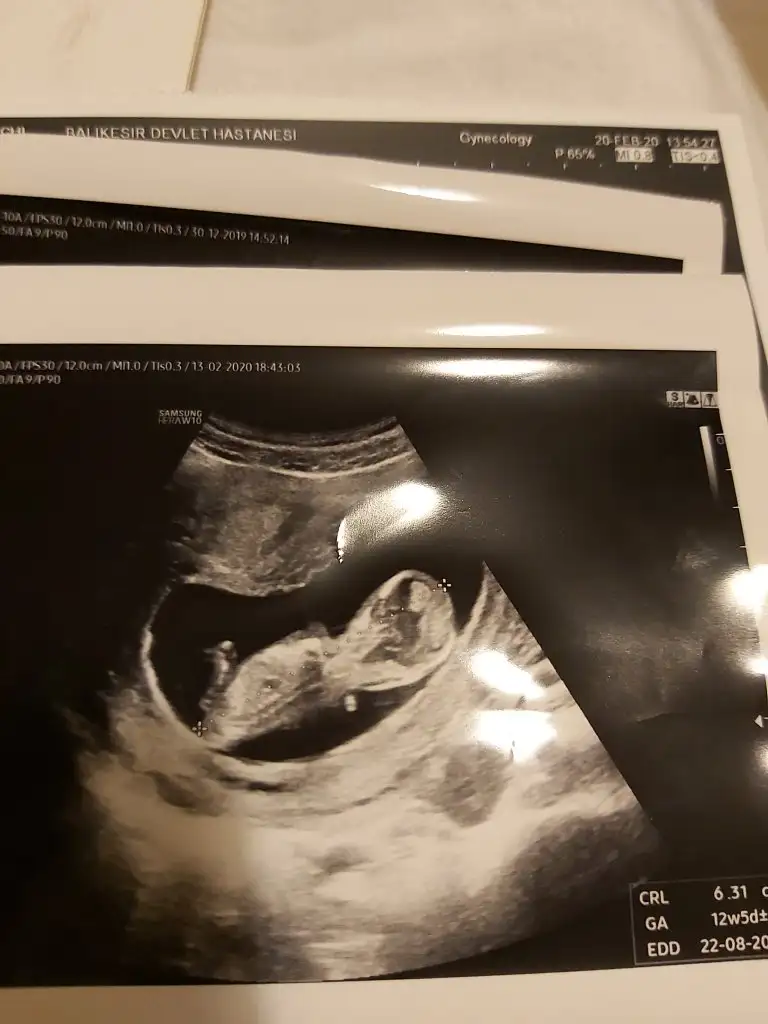

Kız gibi yorumladım eylül annelerinde siz 12+ usgde paylaşınMerhabalarr, eylül anneleri beni buraya yönlendirdi. Tahmin edebilir misiniz acaba rica etsemIkra meyra Eki Görüntüle 2596367

12+5 ve 13+4 usg ler kız gibiIkra meyra 12+5teki fotuyu istemiştiniz ilk foto, 2. Foto 11+5 teki hali bakabilir misiniz?